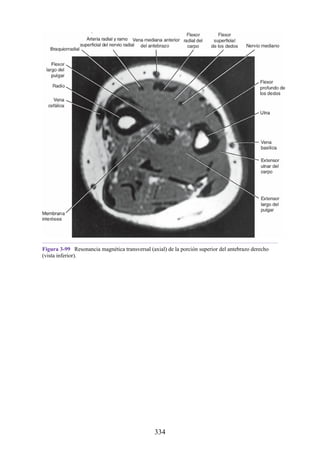

Notas clínicas

Lesiones ligamentosas